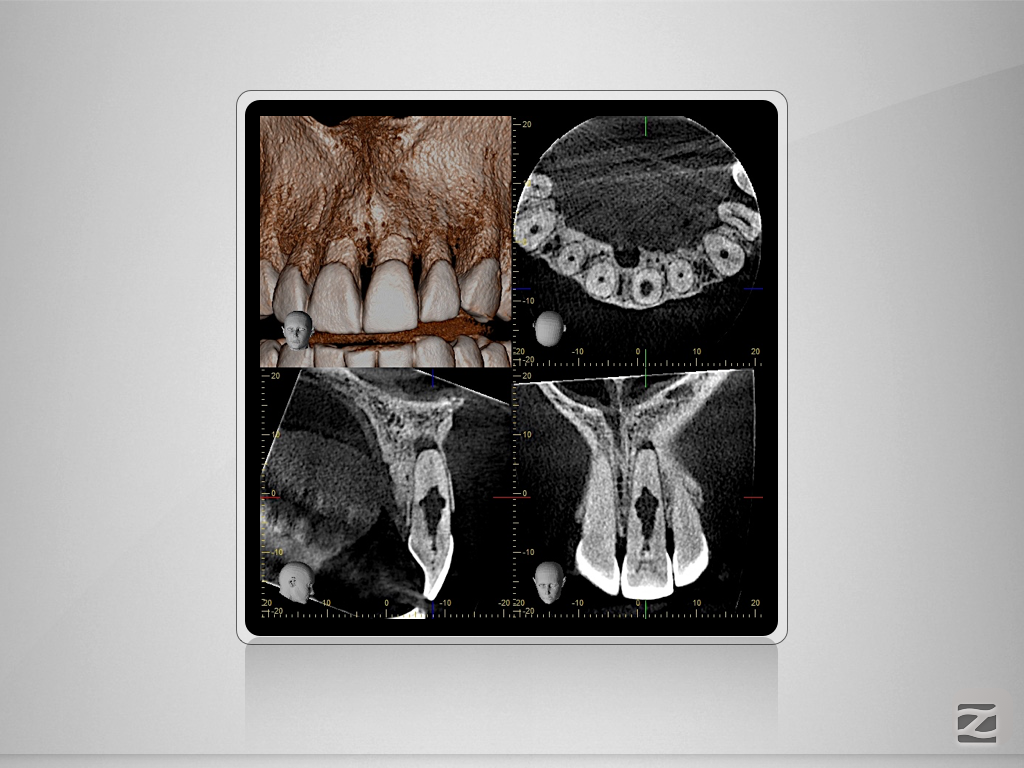

Wie eine Pulpanekrose einen Zahn retten kann.